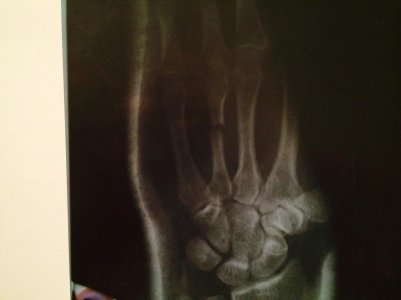

Здравствуйте подскажите пожалуйста! сломал 7 числа на Рождество 4 пястной кости со смещением на левой руке! Наложили гипс сказали прийти через 16 числа! вот прихожу я вчера делают снимок! и говорят срочно нужна операция! Можно ли обойтись без нее? и какие последствия будут если её не делать!

вот снимки последние! E81E22D6-1E54-4F27-9558-D5816481F595.jpg

По данному снимку оперативное лечение не нужно,достаточно гипсовой иммобилизации на 6-7 недель,в дальнейшем возможно использование ортеза.